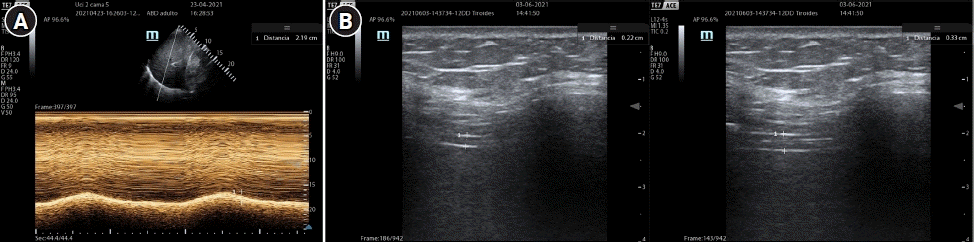

Reverse trigger (RT) described by Akoumianaki et al. [24], refers to the abnormal relation between the MV and diaphragmatic activation, where the external stimulus, the ventilator, provokes a response, that is, diaphragmatic contraction. It can be displayed as two continuous breathings without enough expiratory time, the first one is mandatory by the MV while the second by reflex contraction of the diaphragm (Figure 1A). The main theory of this event explains that flow and pressure applied by the MV activate stretch receptors in upper airways, lungs and chest. As a result, the respiratory center coincides with the phase and frequency of the external stimulus (ventilator) producing a repetitive respiratory pattern [25]. In general, it is more likely to occur during prolonged mechanical lung insufflation, with low flow rates and high volumes. It has been reported that this entity is observed in 50% of patients with acute respiratory distress syndrome (ARDS) during the first 72 hours of MV [26]. When this phenomenon occurs periodically or synchronously with different patterns, it is called “entrainment,” and it can be present in awake sedated patients, even with neuromuscular blockade (NMB), taking place with major frequency when the programed TV and RR are close to the patient’s TV and RR. Its clinical impact will depend on the degree of mismatch between the mechanical cycle and the muscular effort. During RT, the patient’s inspiratory effort begins after the mandatory cycle, and generally, persists beyond it. It has been observed that the maximum expiratory flow is reduced significantly by the presence of inspiratory muscle activation at the beginning of expiration, preventing elastic recoil in the respiratory system.

It is a rare asynchrony compared to insufficient flow asynchrony because it is more likely to program a low flow than a high flow. It is mainly observed in volume-controlled mode, where inspiratory flow is excessive or higher than the patient’s demand, causing overcompensation (Figure 1B). It can also occur in pressure controlled modes, due to high programming of inspiratory pressure (iP) or PS, which generates excessive pressurization. Another option could be a shorter rise time.

Its identification is made more easily in pressure curve: a spike shape or peak will be appreciated on the first part of the inspiratory phase. Its clinical involvement may be minimal, causing only discomfort, however, in PSV mode it can generate early or premature cycling (due to excessively high flow after an inspiratory flow drop), thus shortening inspiratory phase and, consequently, generating an inadequate TV. An alternative to solve this clinical manifestation is to reduce inspiratory flow (in volume control mode) until it meets the patient’s demand or obtains an inspiration/expiration ratio close to 1:2, without causing air trapping. In pressure-controlled modes, decreasing PS or iP assistance, as well as increasing rise time, could represent viable solutions [5,32].